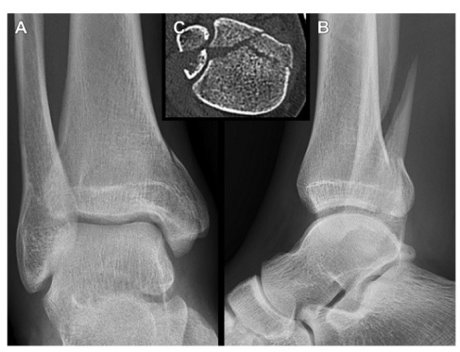

p1 型(腓骨切迹外骨折,腓骨切迹完整):非手术治疗。Haraguchi III 型

p2 型(涉及腓骨切迹的后外侧骨折):解剖复位和固定,特别是有嵌入骨块和高位腓骨骨折(Weber C 型)的情况下,重建腓骨切迹以达到腓骨远端解剖复位并恢复下胫腓联合的稳定性。Haraguchi I 型

p3 型(两部分骨折涉及内踝):切开复位内固定,恢复胫距关节的匹配和稳定、腓骨切迹的完整、下胫腓联合的稳定以及内踝的完整。Haraguchi II 型

p4 型(外侧大的三角骨折块):切开复位内固定以恢复关节面和踝关节稳定。Haraguchi I 型